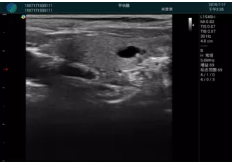

清晰顯示腺體內(nèi)低回聲快影,邊界清晰,包膜較光滑

確定進(jìn)針路徑并實(shí)時(shí)監(jiān)測(cè)抽吸針與腫塊位置關(guān)系

抽吸針進(jìn)入腫塊內(nèi)部進(jìn)行旋切

抽吸過程中可見腫塊明顯縮小,并根據(jù)腫塊位置改變針道位置

抽吸旋切后再進(jìn)行超聲復(fù)查,原腫塊區(qū)域未見殘留組織及出血